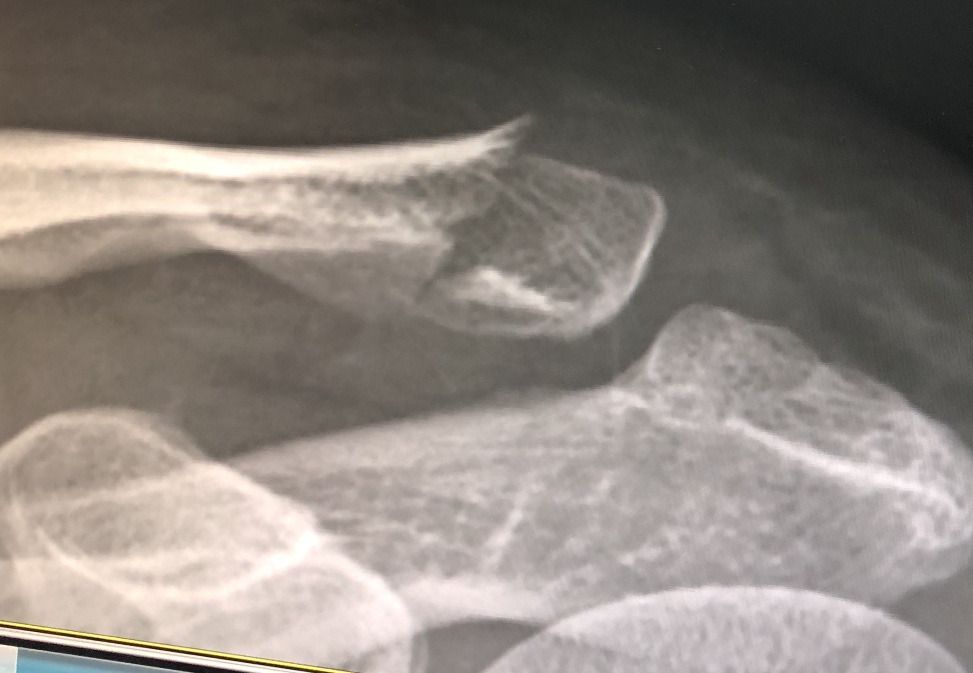

사고직후 골절된 쇄골 원위부